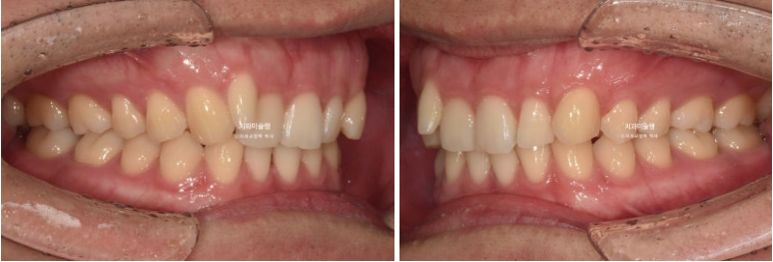

차례대로 교정 완료 직후 - 무삭제 라미네이트 부착 후 - 앞니 끝단 레진 치료 후 사진 입니다.

25년 11월 라미네이트 레진 등 보철을 포함한 모든 치료를 마무리 했습니다.

25.11

중심선은 잘 맞으며

어금니 교합도 좋습니다.

이제 전 후 비교 보겠습니다.

24.03~25.11